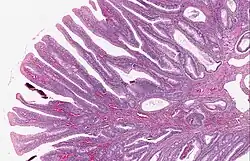

Hyperplastic polyp 0% No dysplasia.[10]

• Mucin-rich type: Serrated ("saw tooth") appearance, containing glands with star-shaped lumina.[11] Crypts that are elongated but straight, narrow and hyperchromatic at the base. All crypts reach to the muscularis mucosae.[11]

• Goblet cell-rich type: Elongated, fat crypts and little to no serration. Filled with goblet cells, extending to surface, which commonly has a tufted appearance.[11]